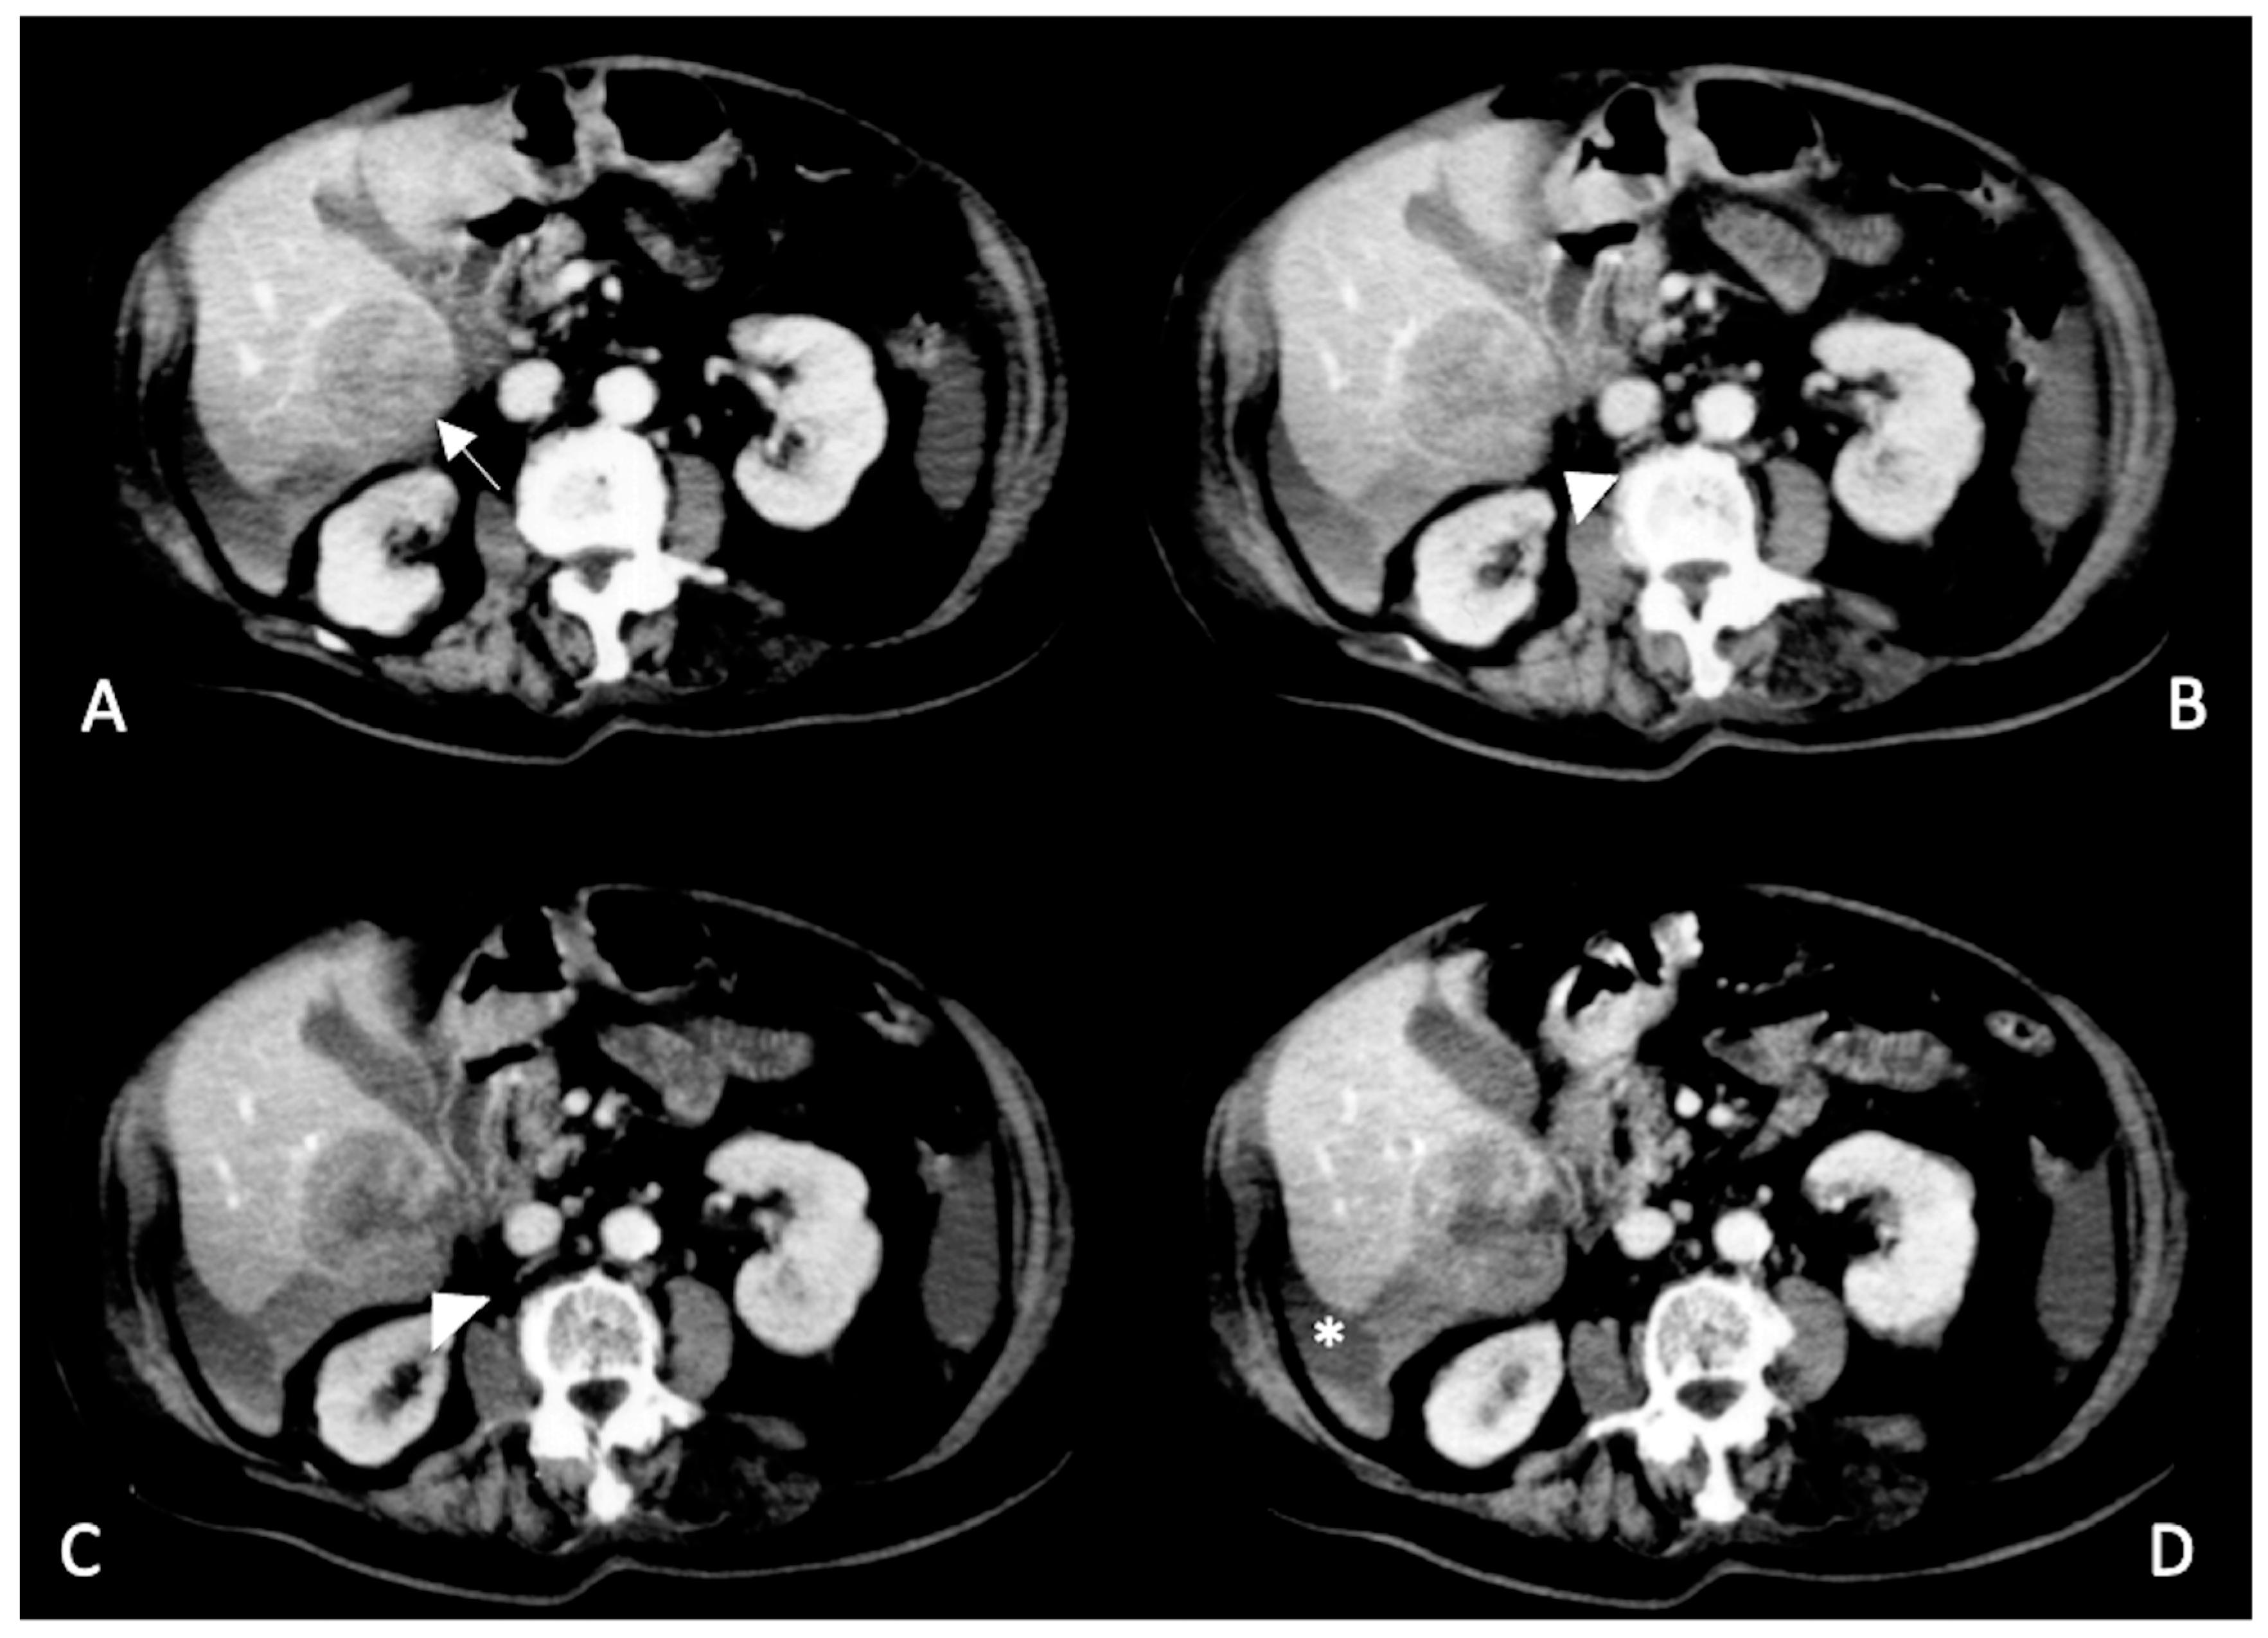

- Kim, H.C.; Yang, D.M.; Jin, W.; Park, S.J. The Various Manifestations of Ruptured Hepatocellular Carcinoma: CT Imaging Findings. Abdom. Imaging 2008, 33, 633–642. [Google Scholar] [CrossRef]

- Furlan, A.; Fakhran, S.; Federle, M.P. Spontaneous Abdominal Hemorrhage: Causes, CT Findings, and Clinical Implications. AJR Am. J. Roentgenol. 2009, 193, 1077–1087. [Google Scholar] [CrossRef] [PubMed]

- Murakami, A.M.; Anderson, S.W.; Soto, J.A.; Kertesz, J.L.; Ozonoff, A.; Rhea, J.T. Active Extravasation of the Abdomen and Pelvis in Trauma Using 64MDCT. Emerg. Radiol. 2009, 16, 375–382. [Google Scholar] [CrossRef]

- Catalano, O.; Lobianco, R.; Esposito, M.; Sandomenico, F.; Siani, A. Contrast media extravasation in upper abdominal injuries: Detection with spiral computerized tomography. Radiol. Med. 1999, 97, 138–143. [Google Scholar]